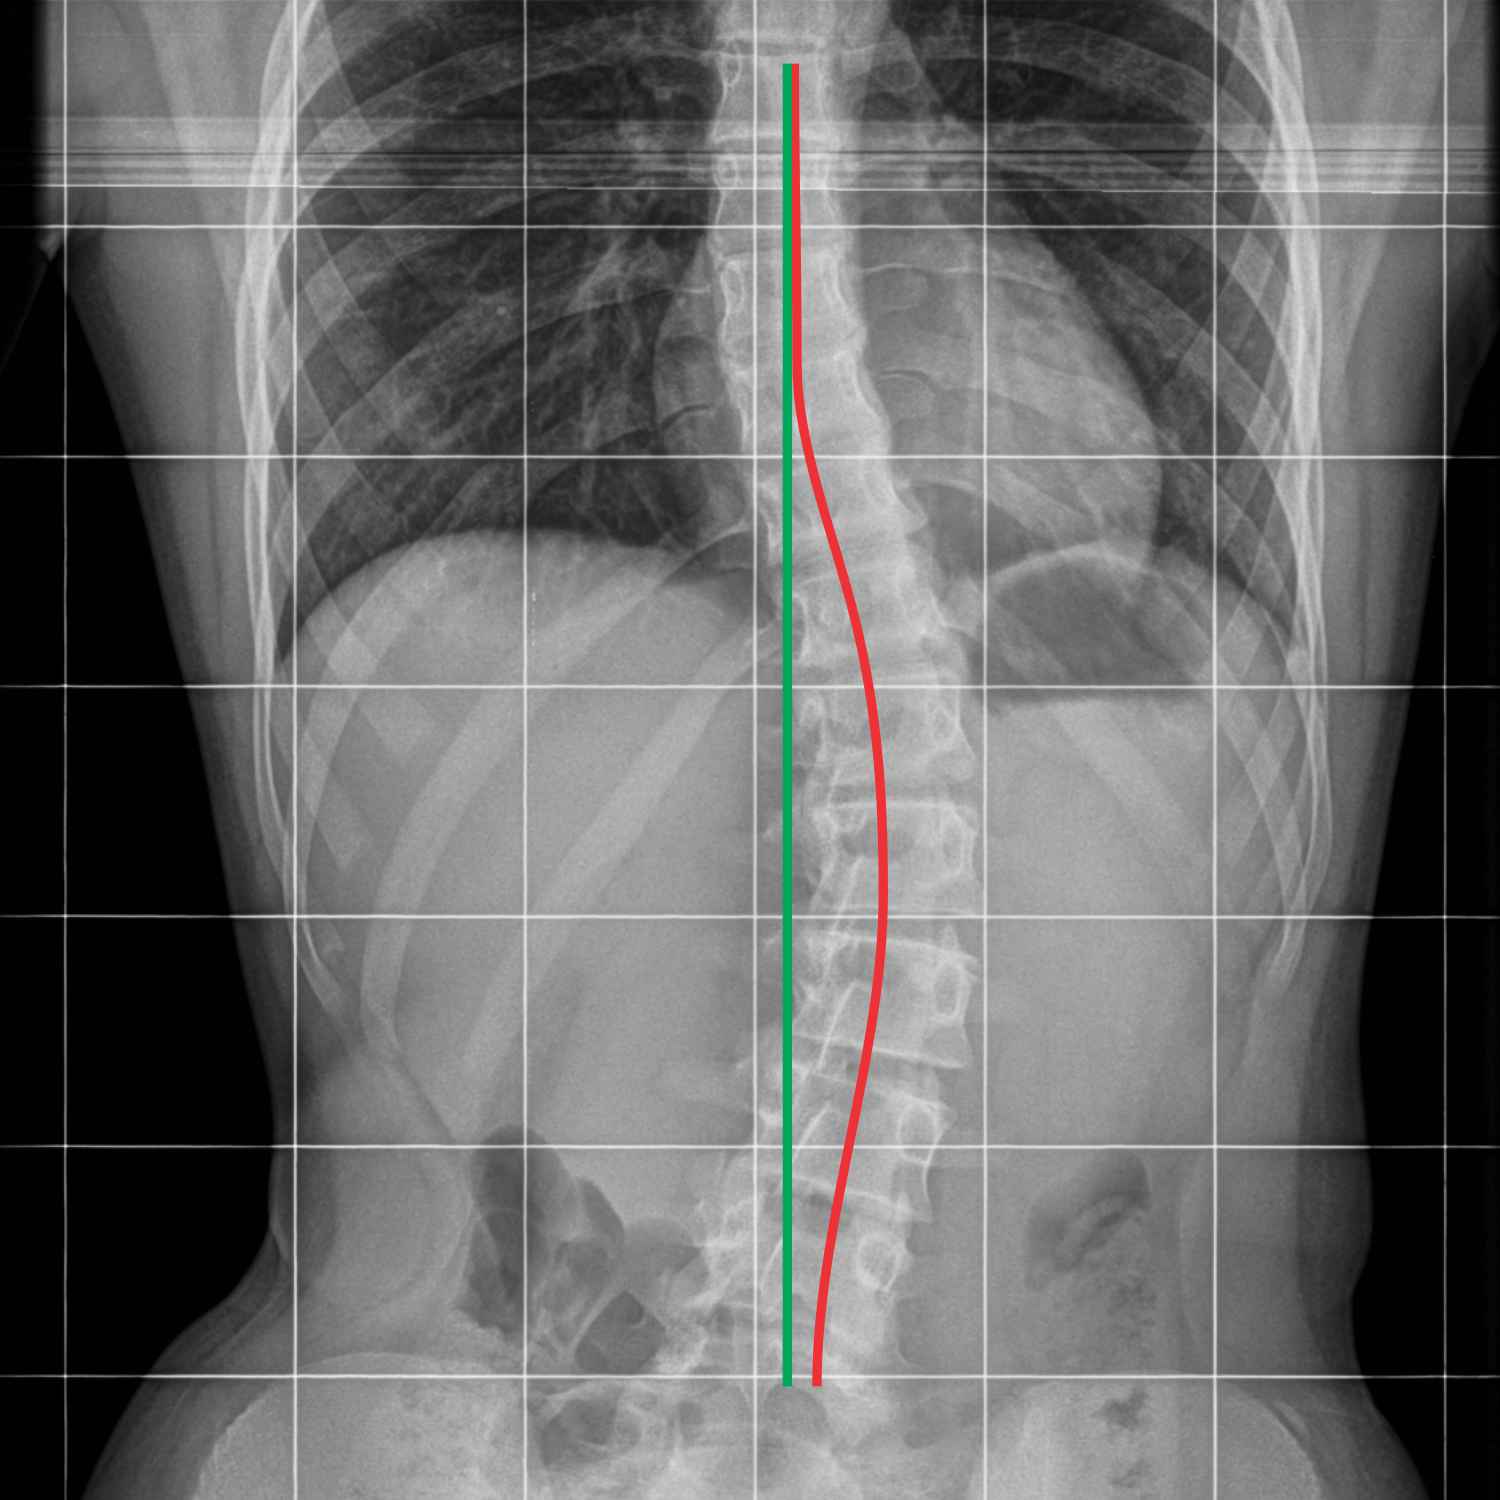

MRI ukrivljenost hrbtenice, skolioza, skolioza vaje, simptomi, zdravljenje

Skolioza

Do zasukane hrbtenice ali skolioze pa lahko pride že v otroštvu. Kako hitro lahko popravimo skoliozo?

Odvisno je, na kateri stopnji je posameznik. Pri skoliozah nikoli ne gre hitro, ker je to stanje podobno, kot če bi bil zamaknjen temelj hiše. Majhen zasuk popravimo z mišicami, ki vlečejo hrbtenico. Mišice je potem treba v tem stanju ohranjati ves čas. Tudi večje ukrivljenosti lahko korigiramo z mišicami, ne moremo pa hrbtenice poravnati. Ljudje s skoliozo morajo zelo natančno in zelo konsistentno delati, potem pa vidimo, koliko telo dopušča. V večini primerov skolioza ni močna in telo dopušča zelo veliko.